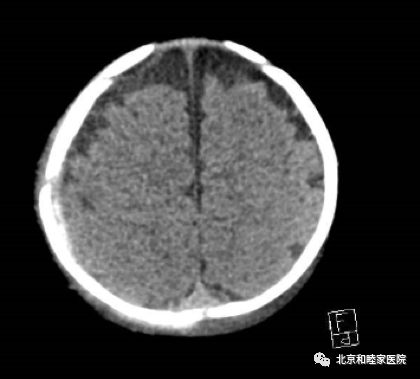

为求进一步治疗,家长带孩子来和睦家急诊进行头颅CT检查,诊断结果显示:右颞、枕、顶骨多发分离骨折伴右侧人字缝部分分离;右颞顶部硬膜外血肿。右顶骨骨折,右颞枕及顶部头皮下血肿。随后患儿收住小儿神经外科ICU接受治疗,完善各项检查,予保守治疗,经过全科医护人员精心治疗,现患儿恢复良好。

患儿入院头颅CT影像